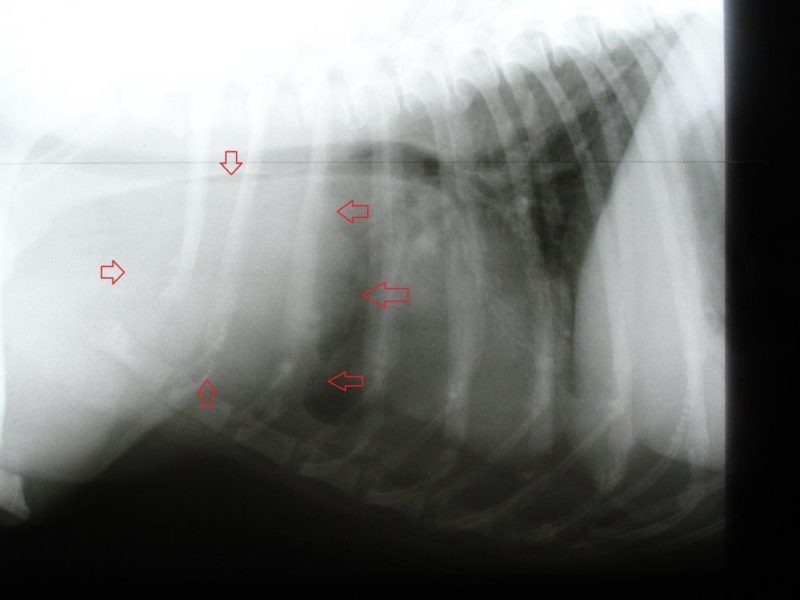

Die Analdrüsen und die äußerlich tastbaren Lymphknoten waren unauffällig. Daraufhin wurden Röntgenaufnahmen von Brust- und Bauchraum angefertigt. Im Brustkorb befand sich vor dem Herzen eine tennisballgroße Zubildung. Zur Diagnosestellung wurde dieser Tumor unter Ultraschallkontrolle mit einer Spritze punktiert und Zellmaterial gewonnen. Dieses Feinnadelaspirat wurde zu einem spezialisierten Tierpathologen geschickt. Der Befund: „Malignes Lymphom“. Das maligne Lymphom kann in einen B- und T-Zell-Typ eingeteilt werden, je nachdem welche Lymphozytenfraktion betroffen ist. In diesem Fall war es das schwieriger zu therapierende T-Zell-Lymphom. Die Ultraschalluntersuchung des Bauchraumes zeigte keine Veränderungen im Bereich von Leber, Milz und den anderen Lymphknoten des Bauches.